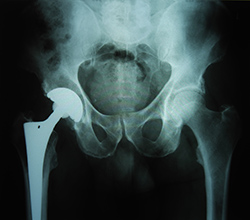

What are the benefits of minimally invasive total hip replacement?

Traditional hip surgery involves making a 20-30 cm incision over the hip, the muscles are split or detached from the hip and the hip is dislocated. This is done so the surgeon can remove the ball joint and insert a metal implant into the femur.

Minimally invasive total hip replacement allows the surgeon to perform the hip replacement through one or two 10 cm incisions. The surgical procedure is similar but there is less dissection of the muscle and soft tissue. As a result the following benefits of minimally invasive total hip replacement have been reported: Read more